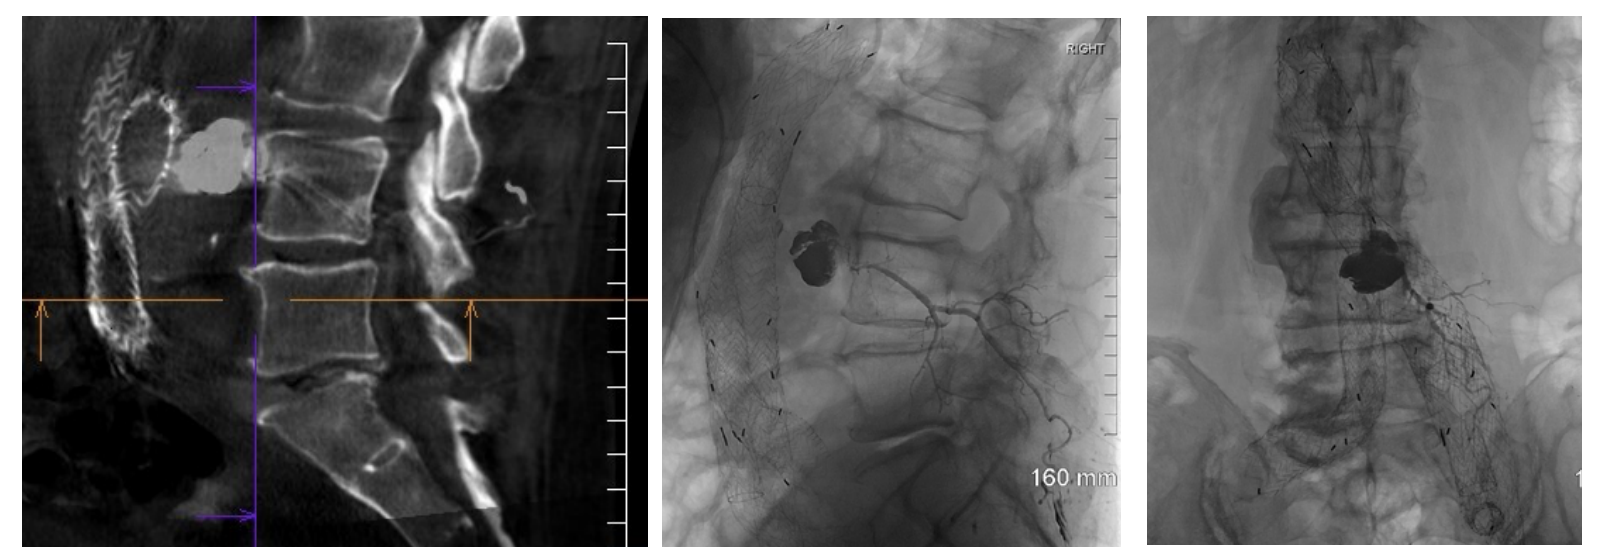

Given the patient’s advanced age and multiple medical co-morbidities, in conjunction with the complexity of his endoleak nidus, the decision was made to utilize advanced navigational software for treatment planning and delivery. The procedure was performed under general anesthesia in the interventional radiology suite. After the patient was secured in a prone position, a cone-beam CT was acquired and multiplanar reconstructions were generated using syngoDynaCT. The pre-intervention CT angiogram dataset was then utilized to estimate the total volume of the endoleak nidus and to identify adjacent vital structures, including the indwelling endograft. The CT angiogram and DynaCT datasets were fused, ultimately creating an overlay of pre-defined regions of interest to be displayed during live 2D fluoroscopy. Lastly, syngo needle guidance software was used to define the ideal needle trajectory (Figure 2). After a skin entry point was identified, a 20-gauge chiba needle was aligned with the integrated laser crosshairs projected onto the patient’s skin. The needle was advanced under direct fluoroscopic guidance, maintaining the x-y coordinates delineated by the navigational software. After gaining sufficient access into the paraspinal soft tissues, the needle guidance software was advanced to display the remaining distance to the target in the z-axis. Once the target was reached, the inner stylet was removed from the needle, and pulsatile blood flow was observed. Extension tubing was connected to the needle hub, and contrast was gently injected under fluoroscopy to confirm positioning within the aneurysm sac. A digital subtraction angiogram was performed, demonstrating opacification of at least one prominent lumbar artery at the L3-L4 level (Figure 3). The needle was flushed with normal saline followed by DMSO (dimethyl-sulfoxide) in preparation for embolization using the Onyx, (Medtronic, Minneapolis, Minnesota), a liquid embolic agent consisting of ethylene vinyl alcohol (EVOH) co-polymer, DMSO, and micronized tantalum powder. Using the integrated overlay showing anticipated nidus volume, a combination of Onyx 18 and Onyx 34 were slowly injected under direct fluoroscopic visualization until the anticipated volume had been reached and the complex iliolumbar collateral network was opacified. In total, 5.6 mL of Onyx 18 (6% EVOH) and 1.4 mL of Onyx 34 (8% EVOH) were administered. The needle was removed, and a final cone-beam CT was obtained to document the extent of the embolic cast (Figure 4).